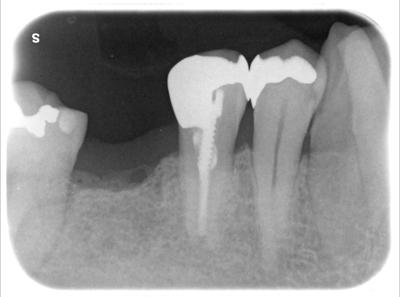

右下7部抜歯、右下5部根管充填後。痛み等の症状は完全消失。

インプラント治療終了、アバットメント試適。

使用インプラントはBiomet 3i(アメリカ)。

5部にはダウエルコア装着。